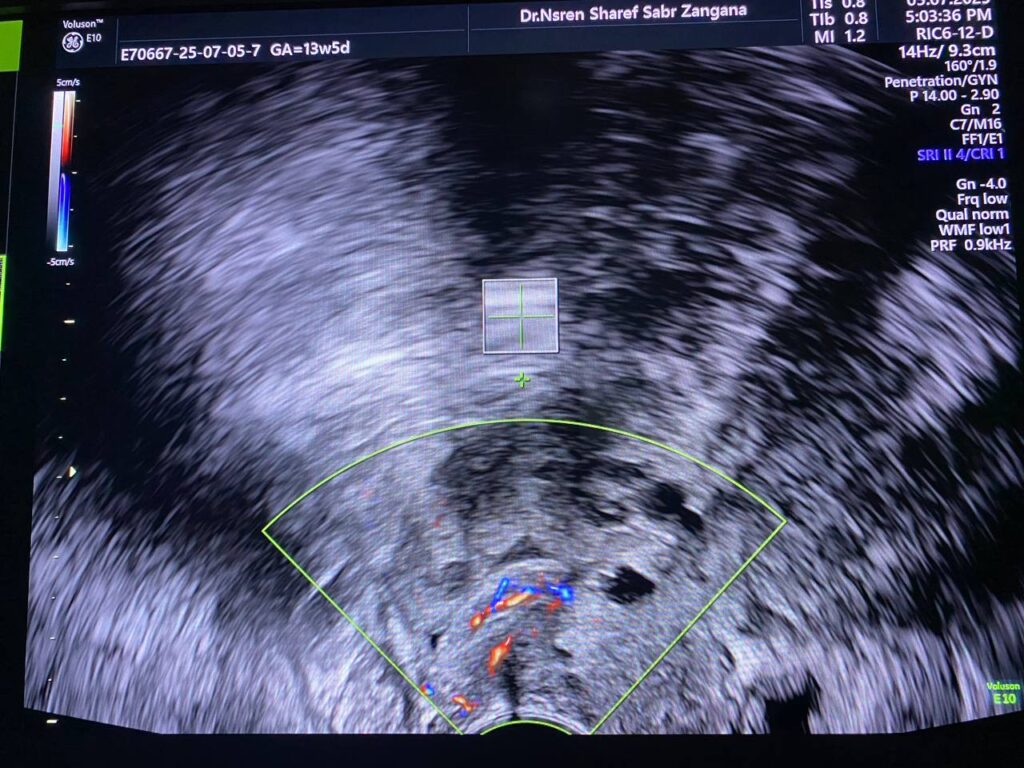

Presence of isoechoic vascular mass 23x6x25mm within the cervical canal , mostly polyp , please for further study to exclude other pathology .

Presence of isoechoic vascular mass 23x6x25mm within the cervical canal , mostly polyp , please for further study to exclude other pathology .